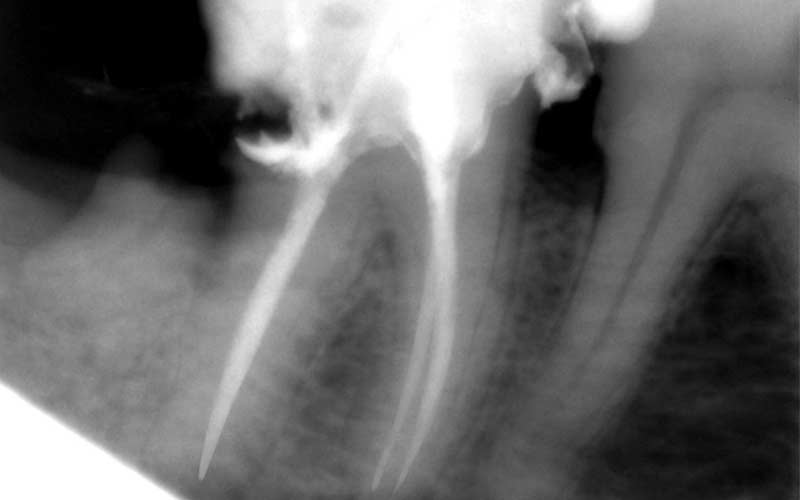

Jep, das war mal ein ungewöhnlicher Schnellauftrag… Für einen Zahnarzt bearbeitete ich eine Handvoll Bilder für ein Buch indem ich vorhandene Röntgen-Aufnahmen im Bereich der Zahnhälse etwas herausgeputzt habe.

Bearbeitung Photoshop mit Kundenunterstützung via Remote Desktop: der Zahnarzt hat so am Telefon genaue Anweisungen gegeben welche Bereiche wie bearbeitete werden sollen.